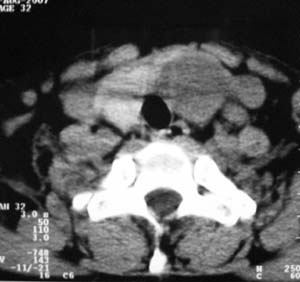

以下是引用zsl6918在2007-8-27 14:40:00的发言:[br]双侧甲状腺多发性低密度占位,边界清晰,密度欠均匀,尤以左侧明显,与周围组织分解清,考虑多发性腺瘤可能性大,不除外结节性甲状腺肿

以下是引用liaizhi在2007-8-27 15:20:00的发言:[br]双侧甲状腺散在多个囊性第密度影,左侧最大一个病灶与正常甲状腺分界尚可,气管受压稍右移。考虑甲状腺瘤的可能性大。